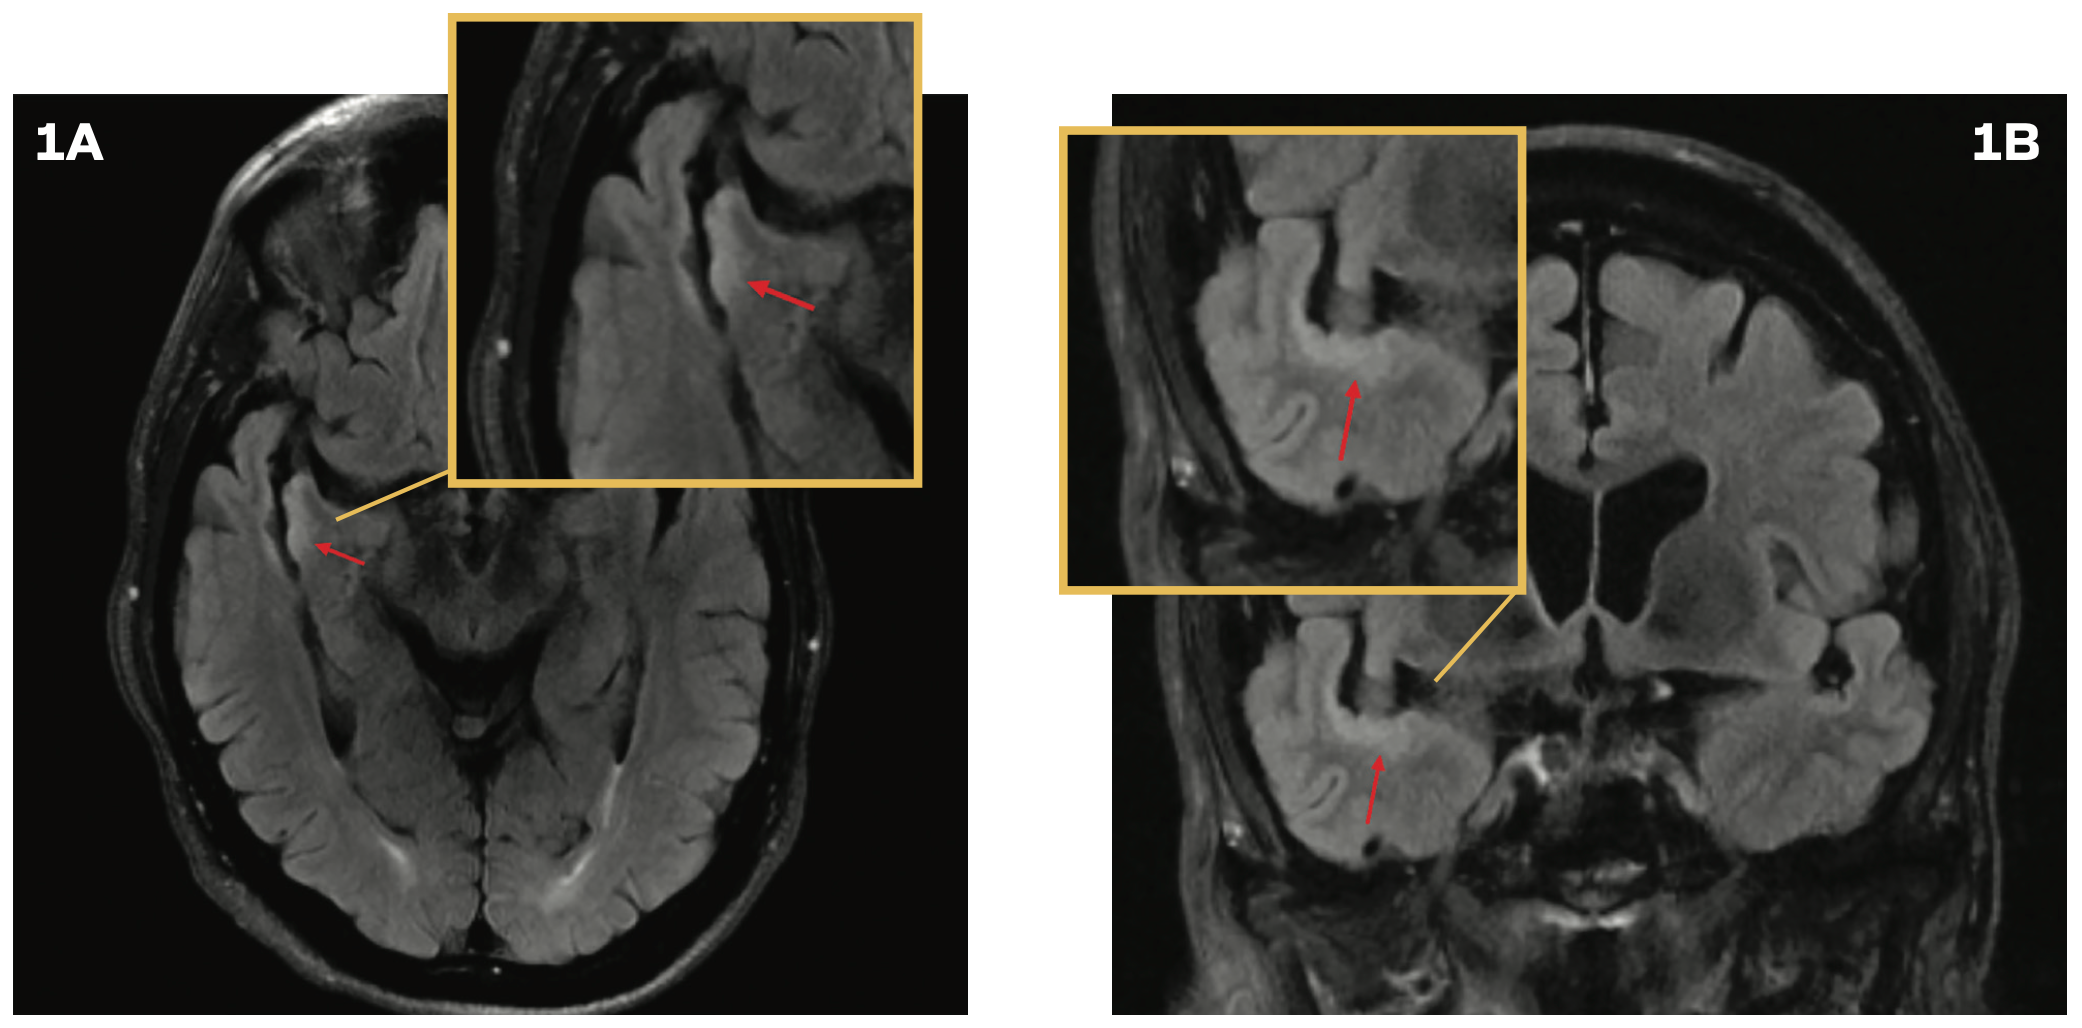

A 76-year-old man was evaluated in the emergency department following a mechanical fall that resulted in a head injury. He experienced a loss of consciousness for approximately 30 seconds. A CT scan of the head revealed no abnormalities. However, the patient continued to experience persistent headaches and dizziness. A brain MRI demonstrated subtle cortical thickening and a contiguous, non–mass-like increased T2 FLAIR signal along the temporal opercular and right insular cortex, without associated enhancement or restricted diffusion (Figures 1A and 1B), prompting a referral to neurosurgery for further evaluation. Subsequent brain MRIs performed 6, 12, and 22 months following the initial imaging did not show progression. However, at a 2.5-year

follow-up, brain imaging revealed progression of the T2 hyperintense abnormality along the ribbon of the superior temporal gyrus (Figures 1C and 1D). The radiographic findings suggested a potential low-grade glioma.

FIGURES 1A AND 1B. Brain MRI With Cortical Thickening

FIGURES 1C AND 1D. Brain Imaging at 2.5 Years’ Follow-Up